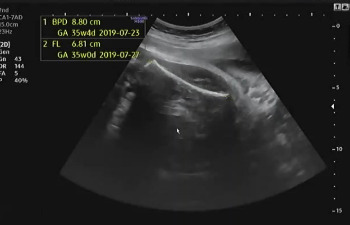

임신 37주가 되어 병원에 내원했다. 초음파를 보는데 아기는 건강하게 잘 있다고 열심히 태동을 하며 인사를 건네 왔다. 머리둘레(BPD), 허벅지 둘레(FL), 복부둘레(AC)를 측정하고 태아가 어느 정도로 성장하였는지 확인했다. 다행히 아기의 머리둘레가 주수보다 작게 나와서 자연 분만하기 좋을 것이라고 이야기를 했다.